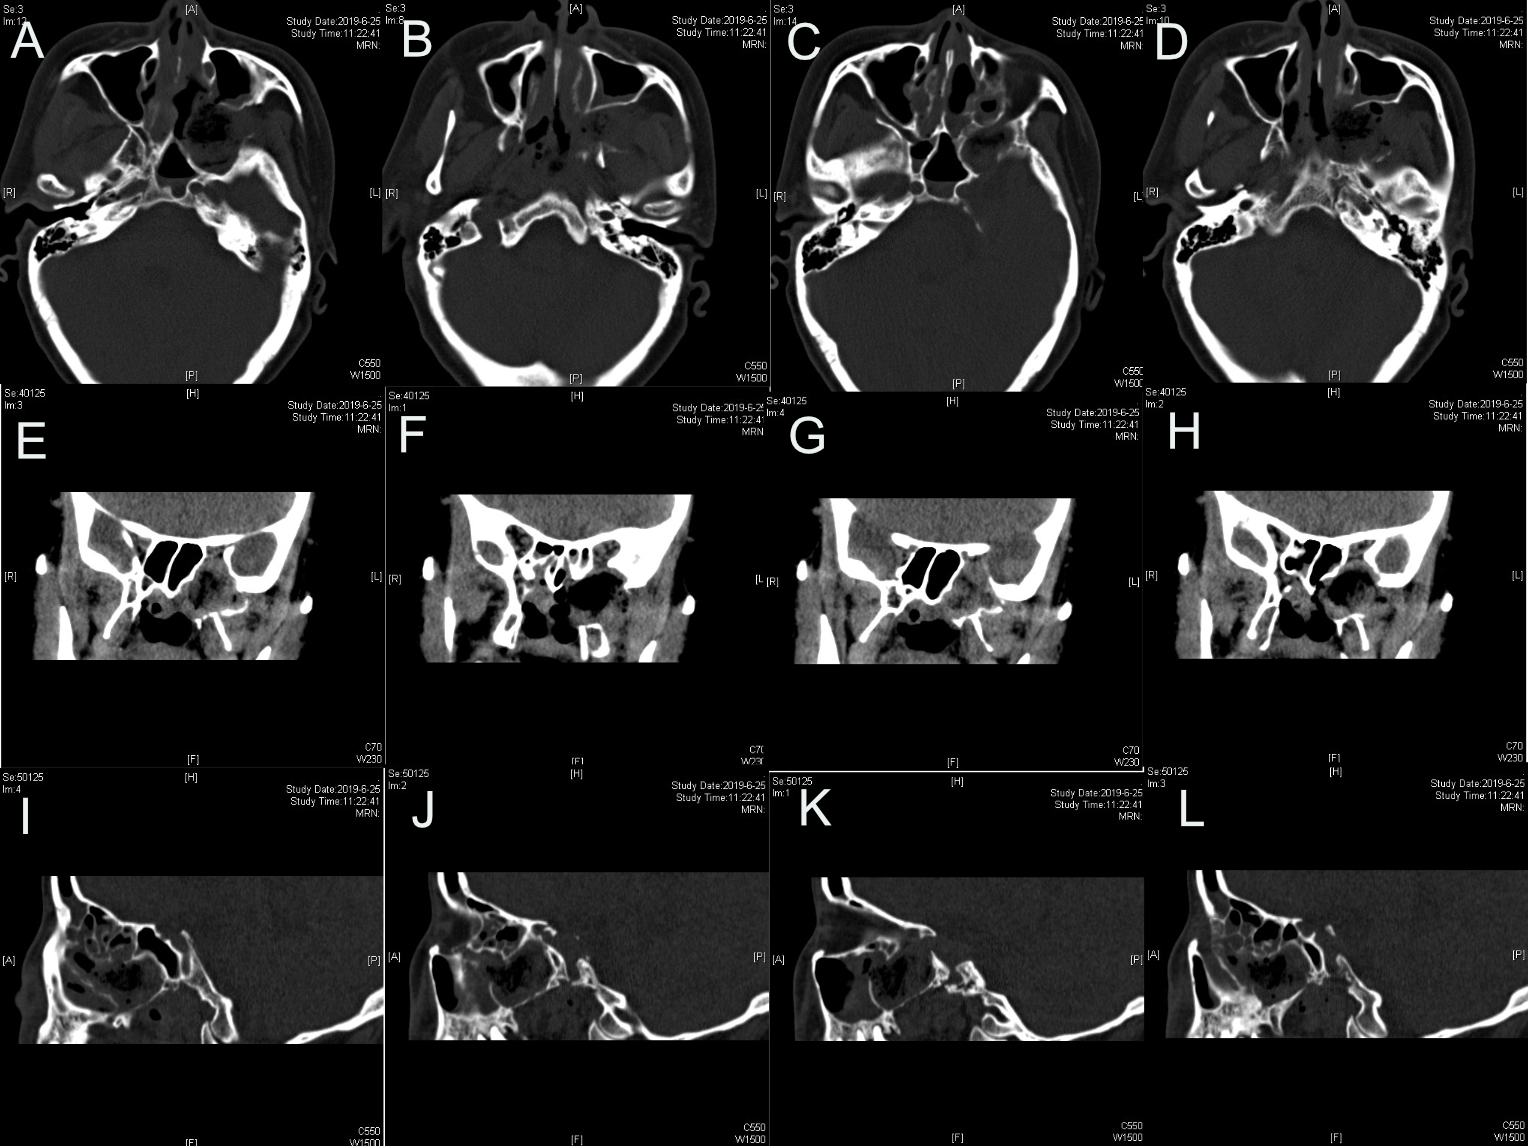

图1.蝶鞍区CT:左侧颅底见梭形软组织密度影,大小约3.7*1.9㎝,周围骨质受压变薄。

图2.PPF内肿瘤侵犯上颌窦后壁以及颞下窝,部分肿瘤向中颅底侵犯。

图12.术后CT左侧颅底术后改变,术区肿瘤完全切除。

图13.左侧颅底术后所见,肿瘤全切除。